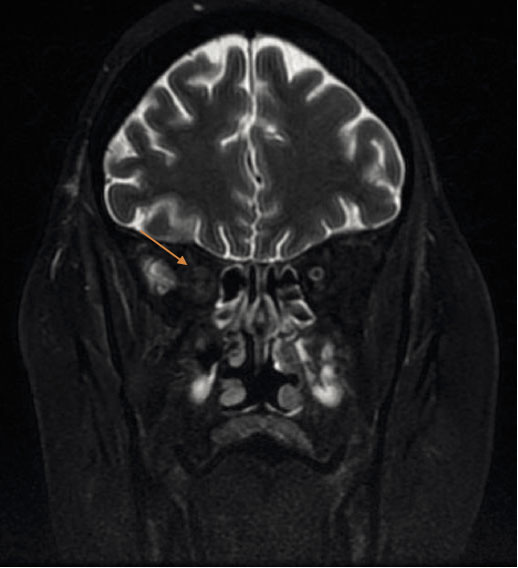

Her complete blood count revealed a hemoglobin of 14.8 g/dL, total white cell count of 9850 /µl, and a platelet count of 408,000 /µl. The erythrocyte sedimentation rate was elevated at 85 mm/hr (normal range 0-30 mm/hr in women over 50). C-reactive protein was 7.3 mg/L. Blood chemistry levels were within normal limits. Urinalysis was normal with no proteinuria or casts. Autoimmune workup was done due to the presence of elevated inflammatory markers. Antinuclear antibody and anti dsDNA were negative. Serum C3 and C4 levels were low. She had a positive rheumatoid factor of 32 IU/ml (normal <15) and positive proteinase 3 antinuclear cytoplasmic antibody (PR-3 ANCA) at >8 AI (normal <1). Anti-myeloperoxidase antibodies were negative. Her chest x-ray was within normal limits. Computed tomography (CT) of the head and sinuses demonstrated bilateral maxillary, ethmoid, and sphenoid sinus opacification without bony erosions. CT angiography of the head and neck was normal. Cerebral magnetic resonance imaging with gadolinium (MRI) showed asymmetric enlargement of the infraorbital and canalicular portion of the right optic nerve suggestive of optic neuritis (Figure 1). No intraparenchymal abnormalities or evidence of venous sinus thrombosis were detected. She had significant meningeal thickening and enhancement in the frontal region that represented pachymeningitis (Figure 2). The patient refused to undergo a lumbar puncture for cerebral spinal fluid studies.

Figure 2

Figure 2. MRI showing significant meningeal thickening and enhancement in the frontal region representing pachymeningitis.